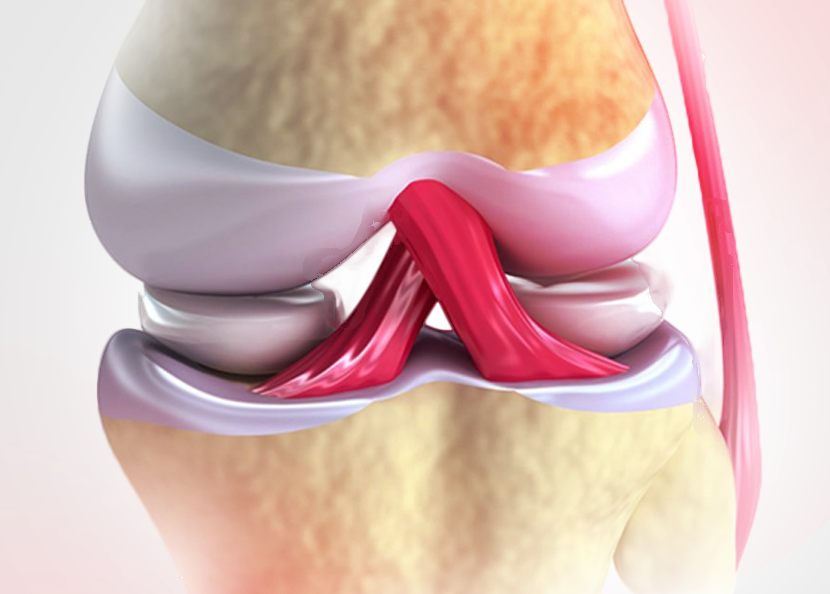

O QUE É O LIGAMENTO CRUZADO ANTERIOR

O ligamento cruzado anterior, ou LCA, é uma estrutura conecta a parte posterior do fêmur com a parte anterior da tíbia, evitando que a tíbia deslize para a frente do fêmur.

Ela é essencial para a movimentação do joelho, tanto nas tarefas de rotina quanto nas atividades esportivas.